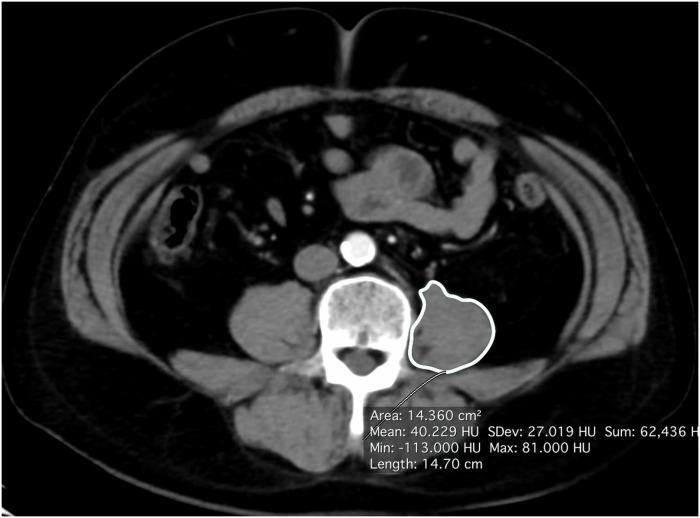

A total of 316 male patients with localized ccRCC who underwent radical nephrectomy at Yokohama City University Hospital (Yokohama, JAPAN) and Kanagawa Cancer Center (Yokohama, JAPAN) between 2002 and 2018 were enrolled in this study. The psoas muscle index (PMI) was calculated by normalizing the psoas muscle area on the contralateral side of the tumor on axial CT, which was calculated at the level of L4 (mm2) divided by the square of the body height (m2). We divided patients into two groups based on the median PMI (409.64mm2/m2).

方法